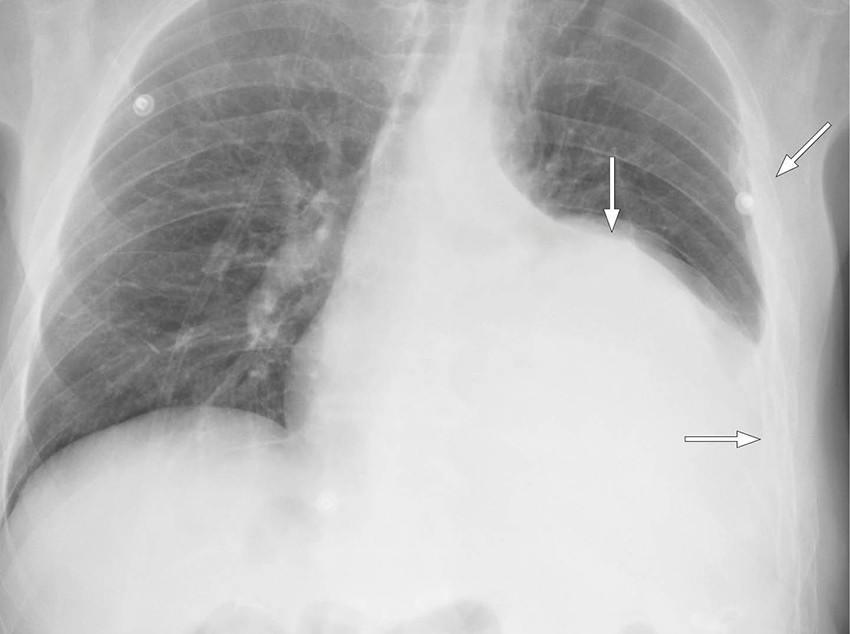

Etter to dagers behandling med alteplase ble pasienten utilpass med smerter i venstre hemithorax. Symptomene lettet da han la seg i sengen. Det ble like etterpå målt blodtrykk på 130/80 mm Hg, puls på 70 slag/min, perifer oksygenmetning på 97 % og registrert 400 mL blodig væske i drenposen. Noen timer senere ble pasienten igjen utilpass, og det ble målt blodtrykksfall til 55/30 mm Hg. Kontroll av hemoglobin viste et fall fra 9,4 til 8,2 g/dL i løpet av dagen. Tilstanden stabiliserte seg med intravenøs væskebehandling og en enhet erytrocytter. Pasienten var våken og blek, og blodtrykket var 100/60 mm Hg. Røntgen thorax viste tiltagende pleuraeffusjon (figur 1), og påfølgende CT thorax konstaterte massiv hemothorax med forskyvning av mediastinum samt en blødningssuspekt lesjon i relasjon til diafragma (figur 2). Tilbake på avdelingen hadde pasienten tiltagende takykardi med puls på 118 slag/min. Blodtrykket var 110/72 mm Hg. Det ble lagt et 28 french-pleuradren akutt og tappet én liter blod.